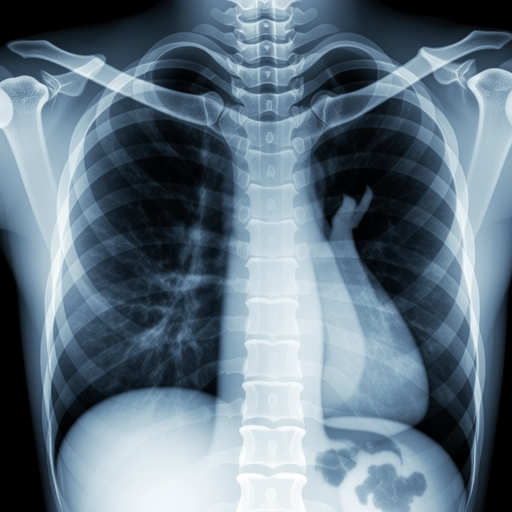

Feline thoracic radiograph showing cardiac silhouette

Figure 3: Feline thoracic radiograph demonstrating proper cardiac silhouette evaluation

Veterinary radiography serves multiple diagnostic purposes across various specialties. Orthopedic evaluations represent approximately 45% of all veterinary radiographic studies, followed by thoracic imaging (30%) and abdominal studies (25%), according to data from the UC Davis Veterinary Medical Teaching Hospital.